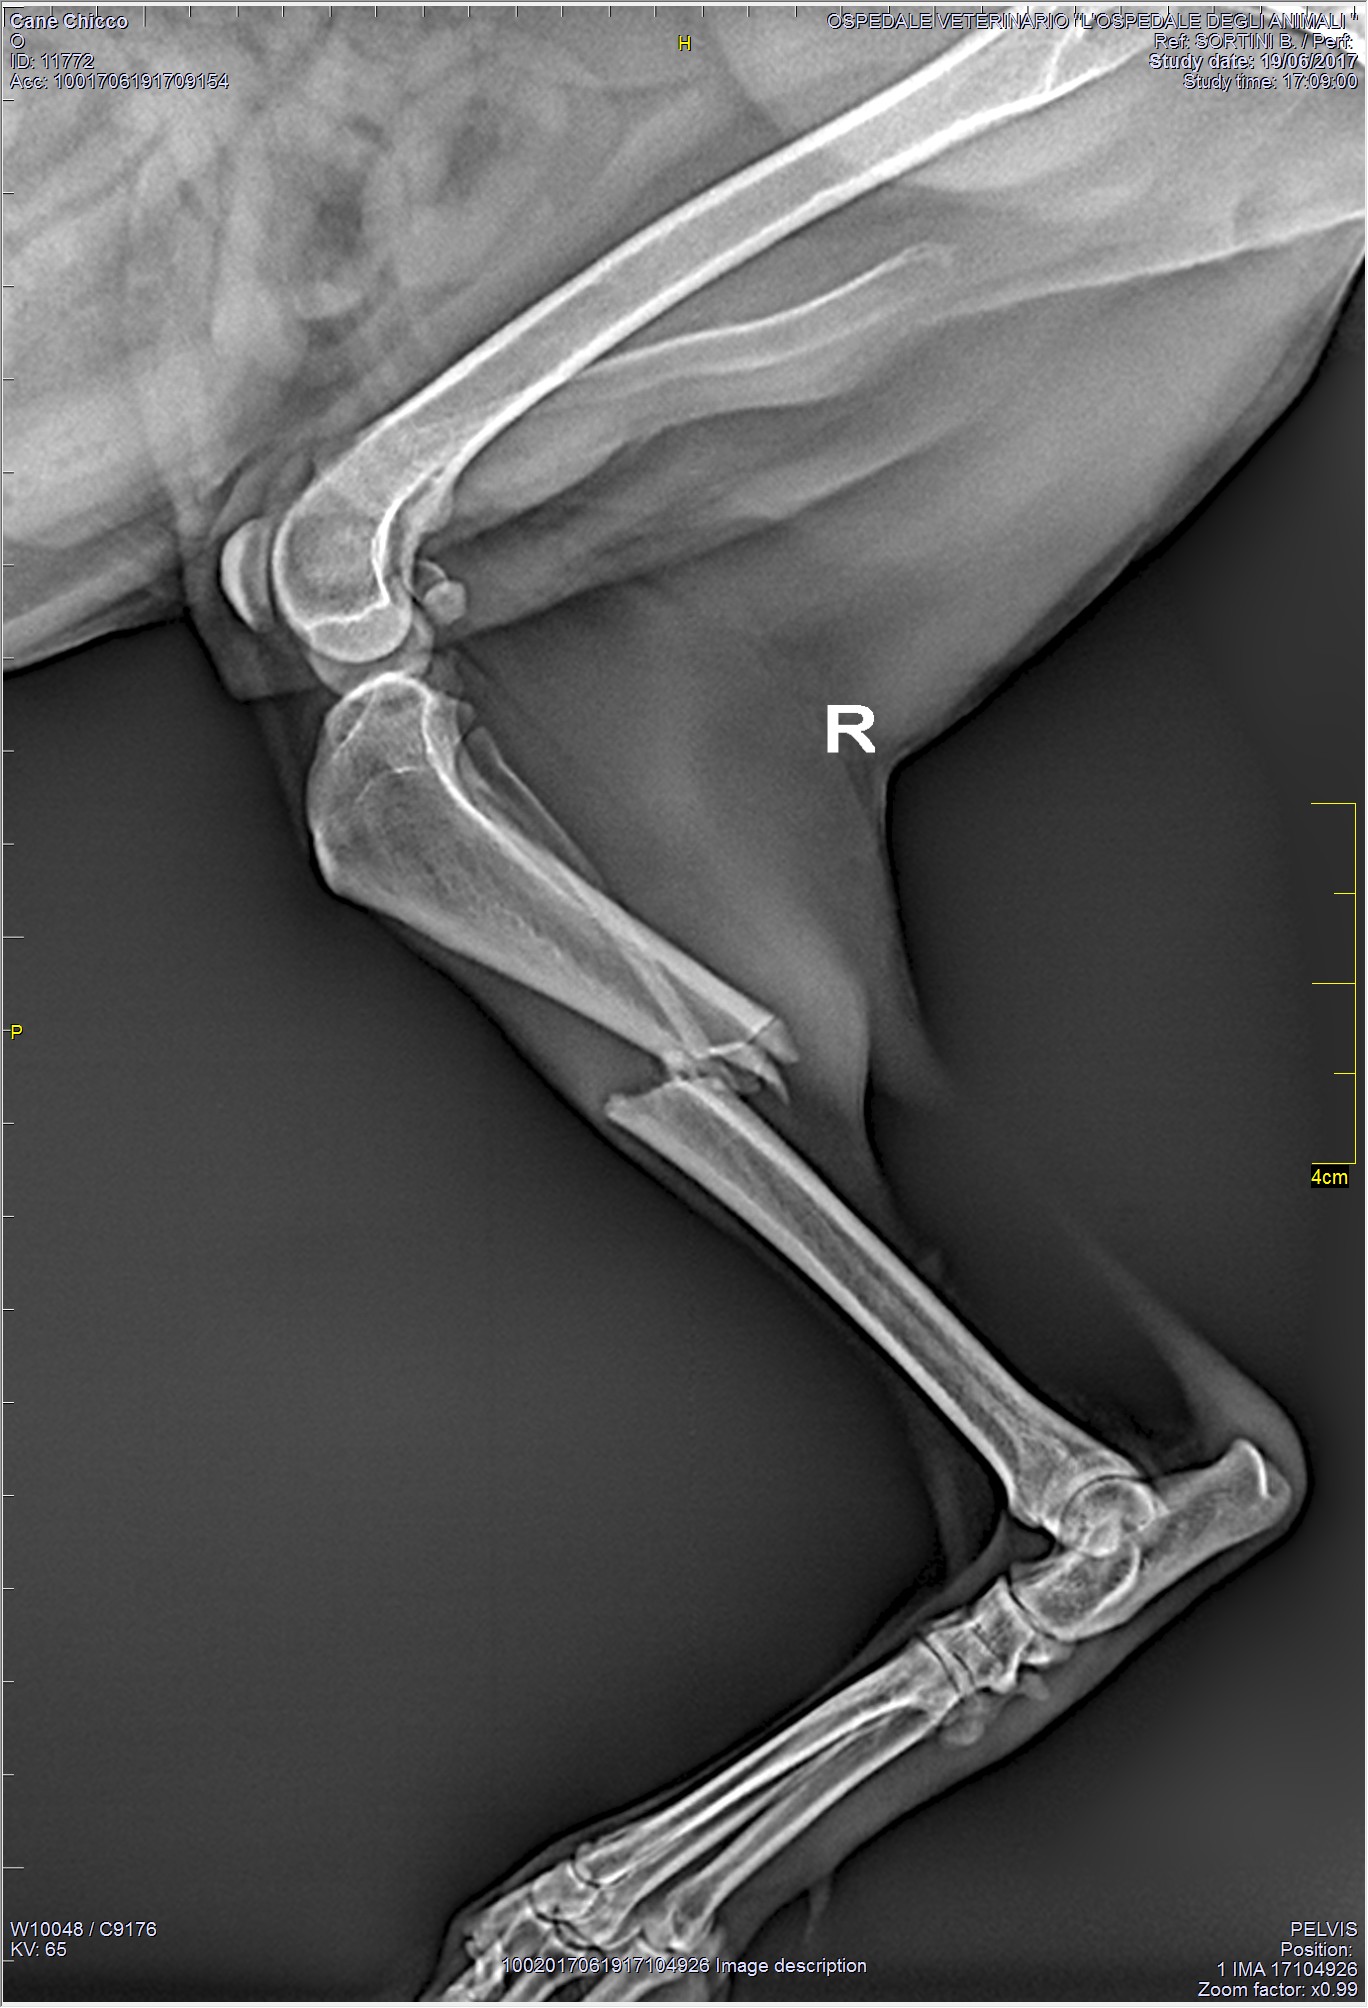

Al momento della visita il medico potrà richiedere eventuali approfondimenti diagnostici: studi radiografici, esami del sangue, ecografie muscolo-scheletriche o esame tac.

La visita clinica e gli approfondimenti diagnostici ci permettono di emettere una diagnosi cui seguirà una terapia, che talvolta prevede un intervento chirurgico specialistico.

La Chirurgia Ortopedica Veterinaria è una disciplina che ha visto, negli anni, una evoluzione esponenziale nelle conoscenze e nelle possibilità di intervento.